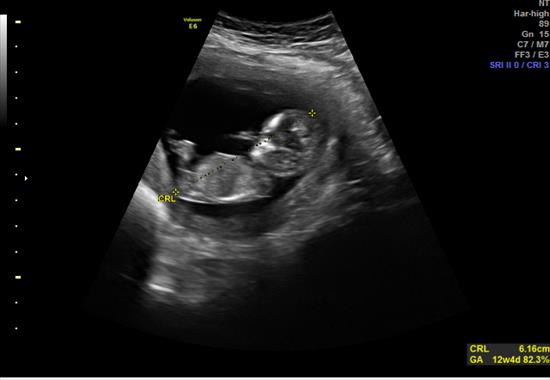

BABY is 12 weeks 4 days...

Attachment 27220

Pink or Blue?

Also -- saw this between the legs, boy parts???